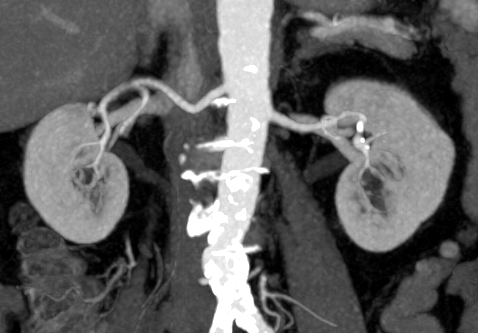

Применение контрастного агента зачастую необходимо в случае проведения первичной дифференциальной диагностики новообразований и уточнения детальной локализации, мониторинге результатов терапевтических/хирургических лечений онкологических заболеваний, а также для оценки сосудистого русла и его физических характеристик. Стоит отметить, что в диагностике сосудистых патологий, таких как мальформации, стенозы и атеросклеротические бляшки данный метод диагностики является “золотым стандартом””.

- Сосудистая система (мальформации, стенозы, повреждения сосудов, атеросклеротические бляшки и кальцификаты). Ранняя диагностика факторов риска развития инсульта;